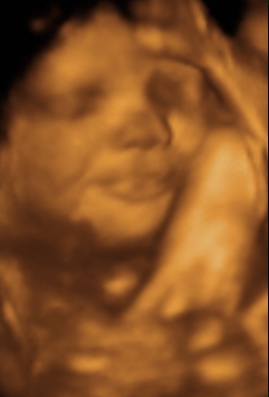

35 week Ultrasound

Friday, July 2nd, 2010

She weighs 5 pounds (2.25kg) and we think she’s pretty cute.